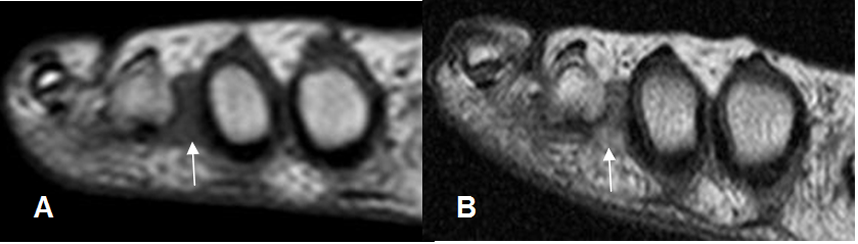

Fig 120. Neuroma de Morton.

A: RM coronal en T2 y B: RM coronal en STIR. Lesión de tejidos blandos entre el 3º y 4º metatarsianos, hipointensa en T2 e hiperintensa en STIR, compatible con neuroma de morton.